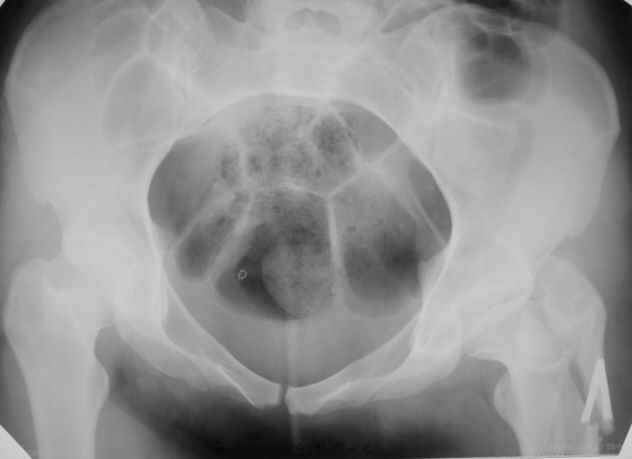

Пациентка 23 лет, доставлена в клинику с Диагнозом: Закрытый сегментарный оскольчатый перелом левой бедренной кости в верхней и средней трети. Травма в результате ДТП 10.03.2006г. Из анамнеза у пациентки диспластический левосторонний коксартроз, S-образный сколиоз 2ст. В 1999г в Кургане выполнялась остеотомия бедра в нижней трети и коррекция укорочения конечности на 3 см (рентгенограммы бедра и таза до травмы в приложении). До получения травмы пациентка ходила без боли с полной нагрузкой на левую ногу. Учитывая дисплазию левого ТБС, пациентке, вероятно, предстоит операция тотального эндопротезирования лев ТБС, что требует анатомичного восстановления проксимальногоотдела бедра. Рассматриваются следующие вариант остеосинтеза:1) Экстракортикальный остеосинтез проксимального и дистального перелома пластиной с угловой стабильностью типа LISS( г Рыбинск); 2) Ретроградный интрамедуллярный блокированный остеосинтез дистального перелома и накостный синтез проксимального пластиной с угловойстабильностью; 3) Остеосинтез бедра в аппарате внешней фиксации с фиксацией таза и возможной открытой адаптацией фрагментов. Хотелось бы узнать Ваше мнение. С уважением Украинский Евгений, г.Краснодар, ККБ N1, ТОО N3.

Не во всех случаях, особенно у молодых!, при дисплазии ТБС требуется эндопротезирование. По представленным снимкам четко видны хорошо сохраненный тазобедренный сустав и тем более больная до травмы не имела симптомов диспластического сустава. В будущем при появлении симптомов, можно попытаться сделать реконструктивную работу по сохранению сустава: ПАО с удлинением шейки (аналогичные случаи были

Учитывая, что в проксимальная часть бедра в скором будущем будет нуждаться в больших оперативных вмешательствах, я бы старался сохранить проксимальное кровообращение бедра и поэтому считаю антеградное штифтование неприемлемым методом для данного случая.